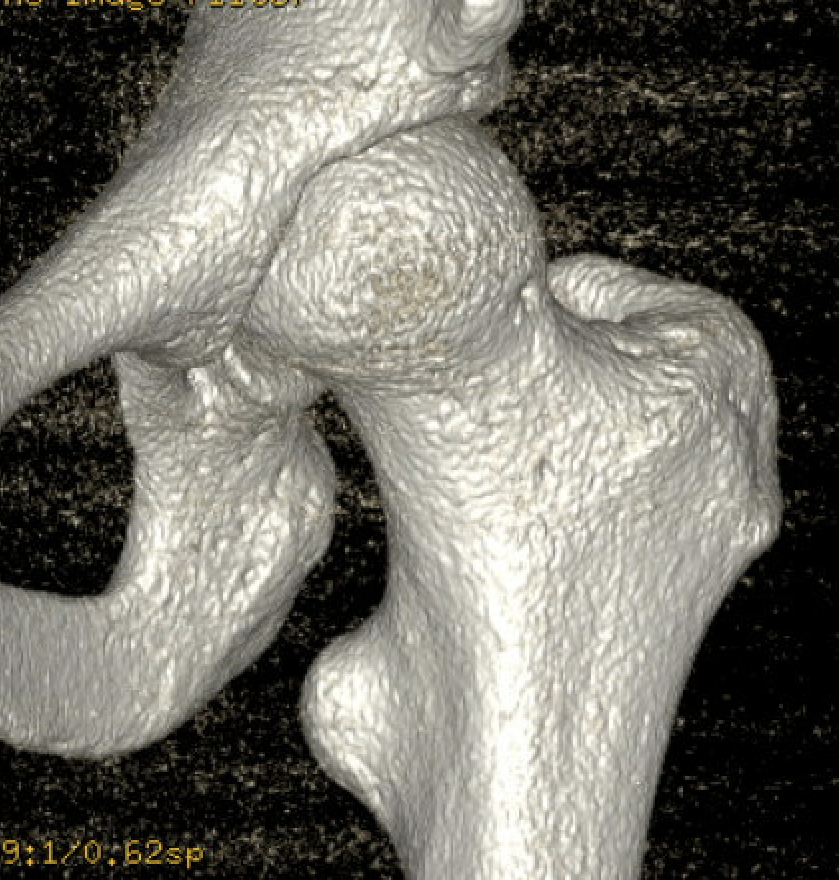

CT

IFI